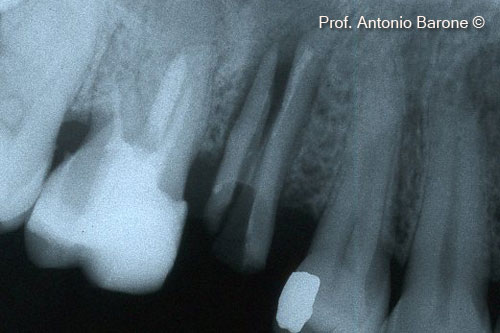

Hình ảnh X-Quang quanh chóp răng cho thấy răng bị gẫy